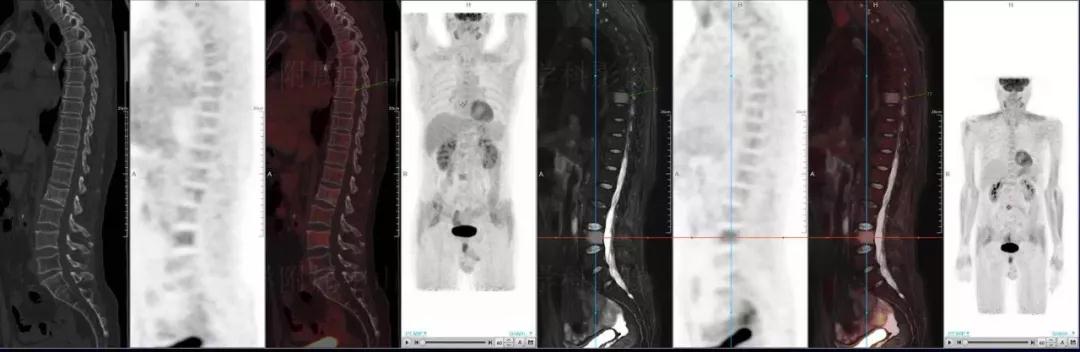

中山醫(yī)院核醫(yī)學(xué)科基于聯(lián)影“時(shí)空一體”超清TOF PET/MR的融合顯像優(yōu)勢(shì),進(jìn)行了大量的臨床掃描,發(fā)現(xiàn)多例由MGUS向多發(fā)性骨髓瘤轉(zhuǎn)變,并從中總結(jié)出了一定的共同征象,未來(lái)可能實(shí)現(xiàn)多發(fā)性骨髓瘤的早期篩查。此外,PET/MR在多發(fā)性骨髓瘤的療效評(píng)估方面,也存在顯著優(yōu)勢(shì)。

(男性,53歲。確診多發(fā)性骨髓瘤10月。經(jīng)過(guò)7周期VCD方案化療后,現(xiàn)行療效評(píng)價(jià)。)